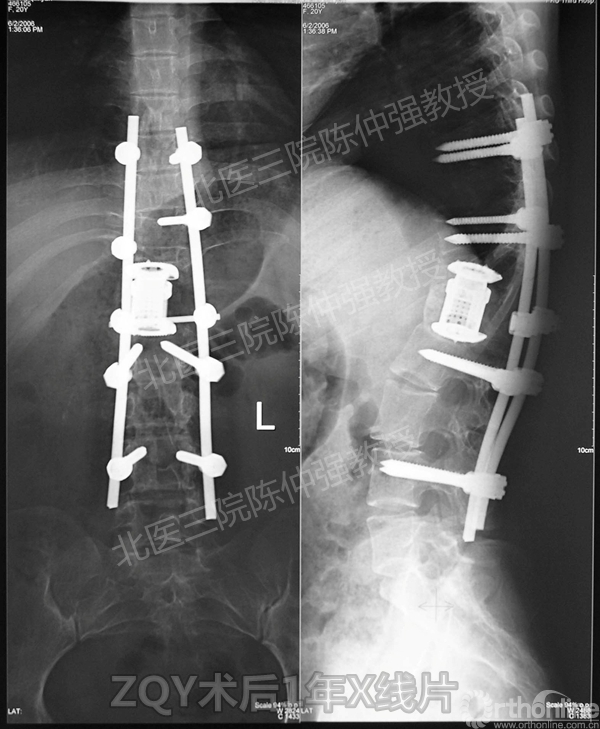

2005年,陈仲强教授在AOSpine年会上分享了一例胸腰椎陈旧结核性侧后凸畸形病例。资料如下:

ZQY术后1年

患者女性17岁,胸腰椎陈旧结核性侧后凸畸形,局部呈“麻花状”扭转,无神经功能受损表现。2005年,陈仲强教授带领团队实施后路+侧前方联合入路脊柱节段切除、双轴旋转矫形术。术后患者外观显著改善,神经功能正常。术后随访证实患者截骨矫形节段骨性融合良好,矫形效果持续良好。